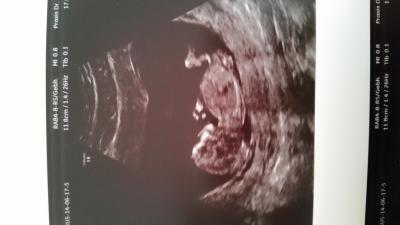

Habe Euch jetzt seit ca. 3 Wochen heimlich beobachtet . Ich hatte gestern auch das Erst Trimester Screening und den wollte ich abwarten. Nach ersten Einschätzungen vom FA ist aber alles gesund und da wo es hin gehört. Naja, nur dass unser Wurm schon sehr groß ist (5,9 cm). Mein FA hatte erst 11+2 (17.06.) berechnet. Gestern meinte er, dass es auch schon 12+2 sein könnte.

Herzlich willkommen. und dir auch eine schöne kugelzeit. Dein foto vom wurm ist echt super schön. Lg schubbel

Ja, der FA hat sich echt Zeit gelassen mit dem Ultraschall. Hat sogar die Finger nachgezählt. Der Papa war auch mit dabei und hat so viel gefragt. War richtig süß (psst... das wollen Männer nicht hören). Könnten sogar erkennen, wie unser Baby sich gestreckt hat.. Es ist echt der Wahnsinn, wie sich alles so entwickelt.

Wowwww, das sieht ja schon echt nach Baby aus, was so 2 Wochen doch ausmachen können. Ich war Montag bei 8+1 zum US, das sah noch nach Wurm aus